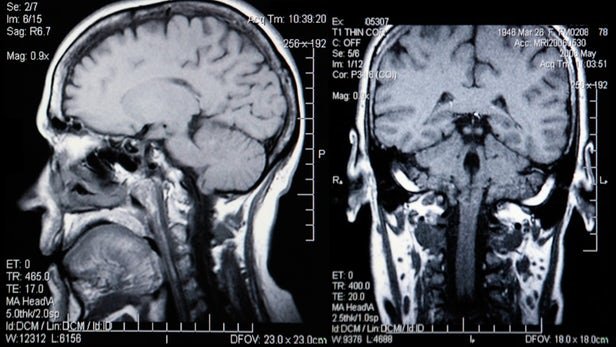

حال محققان دانشگاه انگلیسی موفق شدند با استفاده از اسکن‌های ام.آر.آی و الگوریتم‌های یادگیرنده سن بیولوژیک را محاسبه کنند. روشی که در صورت تایید می‌تواند کار را بسیار ساده‌تر و سریع‌تر کند.

این روش در اصل از سال 2010 آغاز شده و در طی این سال‌ها تکمیل و به روز شده است. الگوریتم‌ مورد استفاده در این تحقیق، با استفاده از بررسی غشای مغز می‌تواند میزان کلی از دست رفتن ماده سفید و خاکستری مغز را که با بالارفتن سن افزایش می‌یابد، پیش‌بینی کند.

با توجه به گزارش منتشر شده از تیم تحقیقاتی چالش موجود در این تحقیق، ایجاد یک استاندارد برای اندازه‌گیری کاهش حجم غشای مغز در ام.آر.آی بوده است.

برای این کار مغز بیش از دو هزار فرد سالم اسکن شده تا محققان بتوانند با انجام مقایسه بین این تصاویر و داده‌های موجود، نرخ تحلیل رفتن مغز را محاسبه کنند.